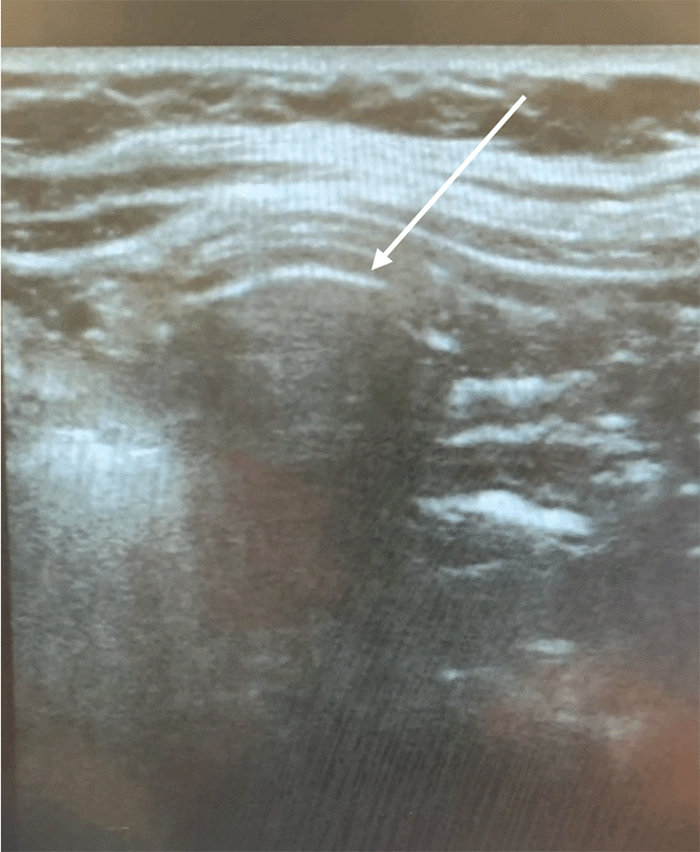

Given the friable nature of the oropharyngeal mass, nasotracheal intubation was performed for patient safety during the procedure. The stomach was fully insufflated during upper endoscopy, and a targeted insertion point was identified with transillumination and indentation. Ultrasound was utilized to assess the proposed insertion point and ensure no underlying solid organs were present between the abdominal wall and stomach. The PEG tube was subsequently placed using the established Ponsky technique. Finally, a concluding ultrasound scan verified proper gastrostomy tube placement, visualizing the bumper within the stomach and confirming the absence of any intervening structures (Figure 2). The patient recovered appropriately from the procedure.

Figure 2. Ultrasound Confirmation of Gastrostomy Tube Placement. Published with Permission

The arrow denotes the interface between the tip of the gastrostomy tube and the stomach mucosa